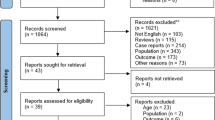

The approaches used to explore the literature and find relevant studies are summarized in Fig. 1. In more detail, the following online resources were searched for relevant articles: Google Scholar and PubMed. The keywords ‘pelvic insufficiency fractures’, ‘cervical carcinoma’ and ‘cervical cancer’, as well as ‘chemoradiotherapy’, ‘chemoradiation’, ‘radiotherapy’, and ‘postoperative’ or ‘post-operative’, were some of the terms used during the search. To gather more literature, we searched the reference lists of previously published reviews and studies that were included in the review. In addition, a manual search approach was carried out as part of this investigation in order to identify other relevant citations that were published in articles. We did not limit our search to any particular time period to collect as much information as possible about PIF after pelvic radiotherapy for cervical cancer.

For this review, we considered studies that met one or more of the following conditions: (1) treated pathologically confirmed cervical neoplasms; (2) documented the incidence, clinical characteristics, and risk factors of PIF after RT; (3) presented a clear overview of the distribution of PIF, (4) articulated treatments to manage PIF complications; and (5) highlighted the limitations of the study.

Studies were not included if (1) they reported only secondary data (such as reviews, study procedures, remarks, or communications); (2) essential data could not be extracted; or (3) they were not published in English.